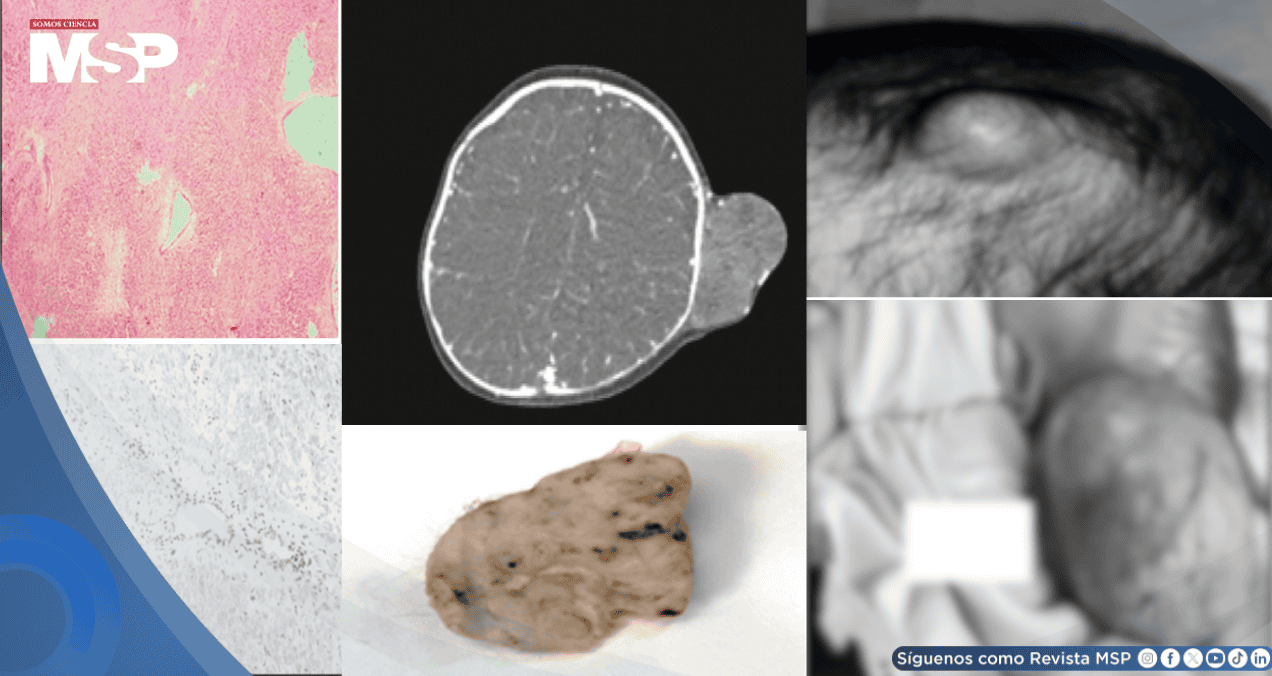

Para caracterizar la naturaleza de la lesión, se realizaron estudios de imagen avanzados. Tanto la tomografía computarizada como la resonancia magnética con contraste evidenciaron una masa que captaba el medio de contraste de forma intensa, un hallazgo conocido como "realce vívido".

Macroscópicamente, la lesión se describió como una masa polipoide, de consistencia firme, cubierta por piel y de dimensiones considerables (11 x 10 x 9 cm). Al ser seccionada, su interior reveló una apariencia sólida y de color blanco tostado, características alejadas de las típicas de un hemangioma.

El examen microscópico del tejido fue determinante. El análisis reveló que la piel estaba infiltrada por células tumorales malignas, dispuestas en láminas. Estas células tenían las características morfológicas distintivas de las células "rabdoides": un citoplasma abundante que contenía inclusiones eosinófilas (glóbulos hialinos), núcleos vesiculares (de apariencia clara) y nucléolos muy prominentes.

El estroma circundante era de tipo fibromixoide y se observaba una alta actividad de células en división (actividad mitótica), junto con áreas de muerte celular (necrosis).

Para confirmar el diagnóstico y descartar otros tumores con apariencia similar, se realizó una batería de tinciones inmunohistoquímicas. Este estudio mostró que las células tumorales eran positivas para marcadores como vimentina, CD99, glipicano-3, sinaptofisina, WT-1, citoqueratina (CK) y EMA.

Sin embargo, el hallazgo clave fue la pérdida de la expresión de la proteína INI-1 en el núcleo de las células tumorales, un sello patognomónico de los tumores rabdoides. Otras tinciones para descartar diagnósticos diferenciales (como CD31, desmina, S100, etc.) resultaron negativas.